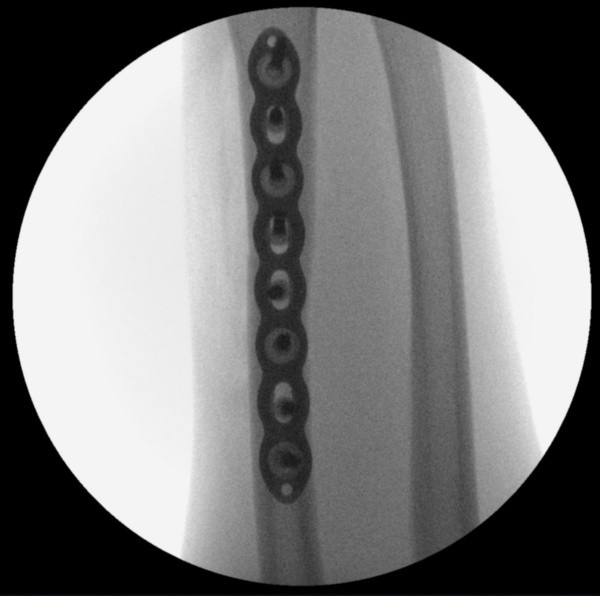

VEJA IMAGENS DA TOMOGRAFIA PRÉ-OPERATÓRIA E DAS RADIOGRAFIAS PÓS-OPERATÓRIAS:

Após a cirurgia, com as placas e parafusos (Foto: Divulgação)